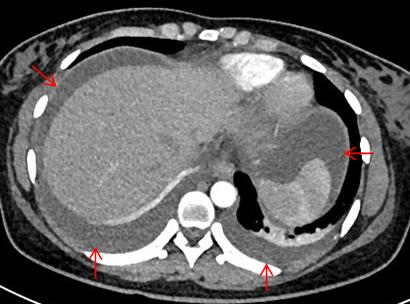

图2. 风湿免疫指标办好住院已经是1月13日下午四点了,介入科方淳主任及团队加班加点,当天晚上就为患者做了肠系膜动脉和静脉造影,结果没有发现大血管的问题,但是小血管充血、丰富,呈梳子样改变(称为“梳子征”,图1)。排除了肠系膜大血管的问题之后,高度怀疑肠系膜小血管炎可能,事不宜迟,赵家胜主任通过电话联系到风湿免疫科值夜班的王璇主治医生,王医生仔细询问了病史,了解到患者有过脱发和自发性流产的病史,结合本次肠道小血管炎的表现,高度怀疑系统性红斑狼疮引起的肠系膜血管炎。为了缓解患者的腹痛,挽救病人的生命,王璇医生基于对病情的判断,在化验结果尚未出来的情况下果断使用了糖皮质激素,第二天早上(1月14日)患者腹痛和恶心、呕吐即明显好转,患者胃口也开了,随后吃了点半流质,但下午又出现了腹痛和呕吐,这时化验结果也出来了(见图2),狼疮的标志性抗体-抗Sm抗体和ds-DNA抗体均阳性,证实了系统性红斑狼疮的诊断。赵主任和风湿免疫科汤建平主任共同查房后认为系统性红斑狼疮诊断明确,以急性腹痛起病,而且一发病就表现为狼疮危象的红斑狼疮少见,常规剂量激素疗效不佳,腹部CT结果显示肠壁水肿和胸腹水有进展(见图3、图4),需要立即进行大剂量激素冲击治疗。

图4. 治疗前胸腹水(箭头所示)